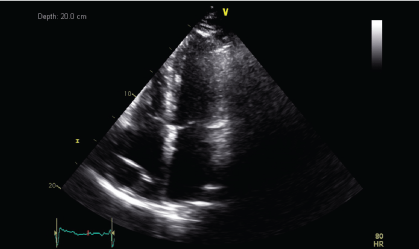

A CT guided biopsy of the right supracondylar femur showed intertrabecular fibrosis with small clusters of CD 163 and CD 68 immunopositive foamy macrophages. No giant cells, eosinophils, or features of Langerhans cell histiocytosis were present. S100, CD 1a immunostaining were negative, and BRAF v600e was positive. These features were consistent with ECD. A two-dimensional echocardiography performed showed a normal left ventricular ejection fraction of 70% with a right atrial mass of 2.5 × 1.3 cm at the posterior wall and another at the lateral wall, which was not visualized on the PET-CT performed. During the course of his stay, a pacemaker was inserted as he developed ventricular fibrillation and bradycardia with sinus pause associated with multiple episodes of syncope.

Figure 4a: Transthoracic echocardiogram (TTE) showing mass lesion in the right atrium close to the tricuspid valve and at the posterior wall (June 2013).

Figure 4b: TTE showing persistent mass lesion in the right atrium close to the tricuspid valve and at the posterior wall (March 2014).

Upon histopathological confirmation of ECD, the patient was given subcutaneous peginterferon-α of 180 mcg once/week and prednisolone of 1 mg/kg/day. After 3 months of treatment, his shortness of breath and joint pain resolved. Repeat laboratory test showed declining ESR of 29 mm/hr and a repeat PET-CT scan showed significant improvement in pericardial soft tissue thickening encasing the thoracic aorta and coronary arteries, with skeletal lesions also showing quantitative reduction of the metabolic activity (Figure 3a and Figure 3b) and no new hypermetabolic lesions. (Table 1). A repeated two- dimensional echocardiogram 18 months later showed regression of the right atrial mass (Figure 4a, Figure 4b, Figure 4c and Figure 4d).